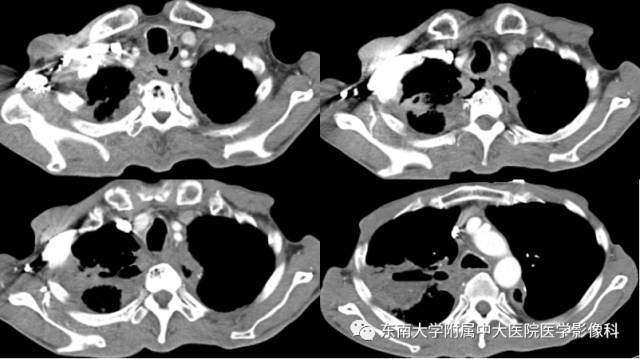

男,60岁,因“食管癌术后5年余,进食呛咳10天”入院。

影像学表现